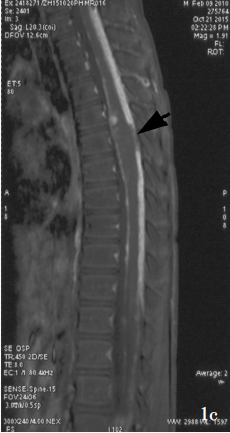

这些肿瘤在MRI T2加权像上表现为高信号。1/2的病例存在囊肿,约1/3的病例存在钙化。对比增强程度不一,可能无强化,也可能明显强化,可能是病灶实体或边缘强化。

大多数中央神经细胞瘤是多囊性肿瘤且有钙化,以宽基底附着在脑室上外侧壁上。它们通常位于侧脑室或三脑室,附着于室间孔附近的透明隔或脑室壁上。但通常不会出现在侧脑室枕角或颞角。

典型的CT表现是脑室内不均匀的高密度肿块,伴有中等对比增强。MRI T1加权像表现为轻度高信号,T2加权像表现在某种程度上更加多变。使用钆后通常增强。可能难以通过MRI区分中央神经细胞瘤、脑室外神经细胞瘤与更常见的病灶(像高级别胶质瘤)。